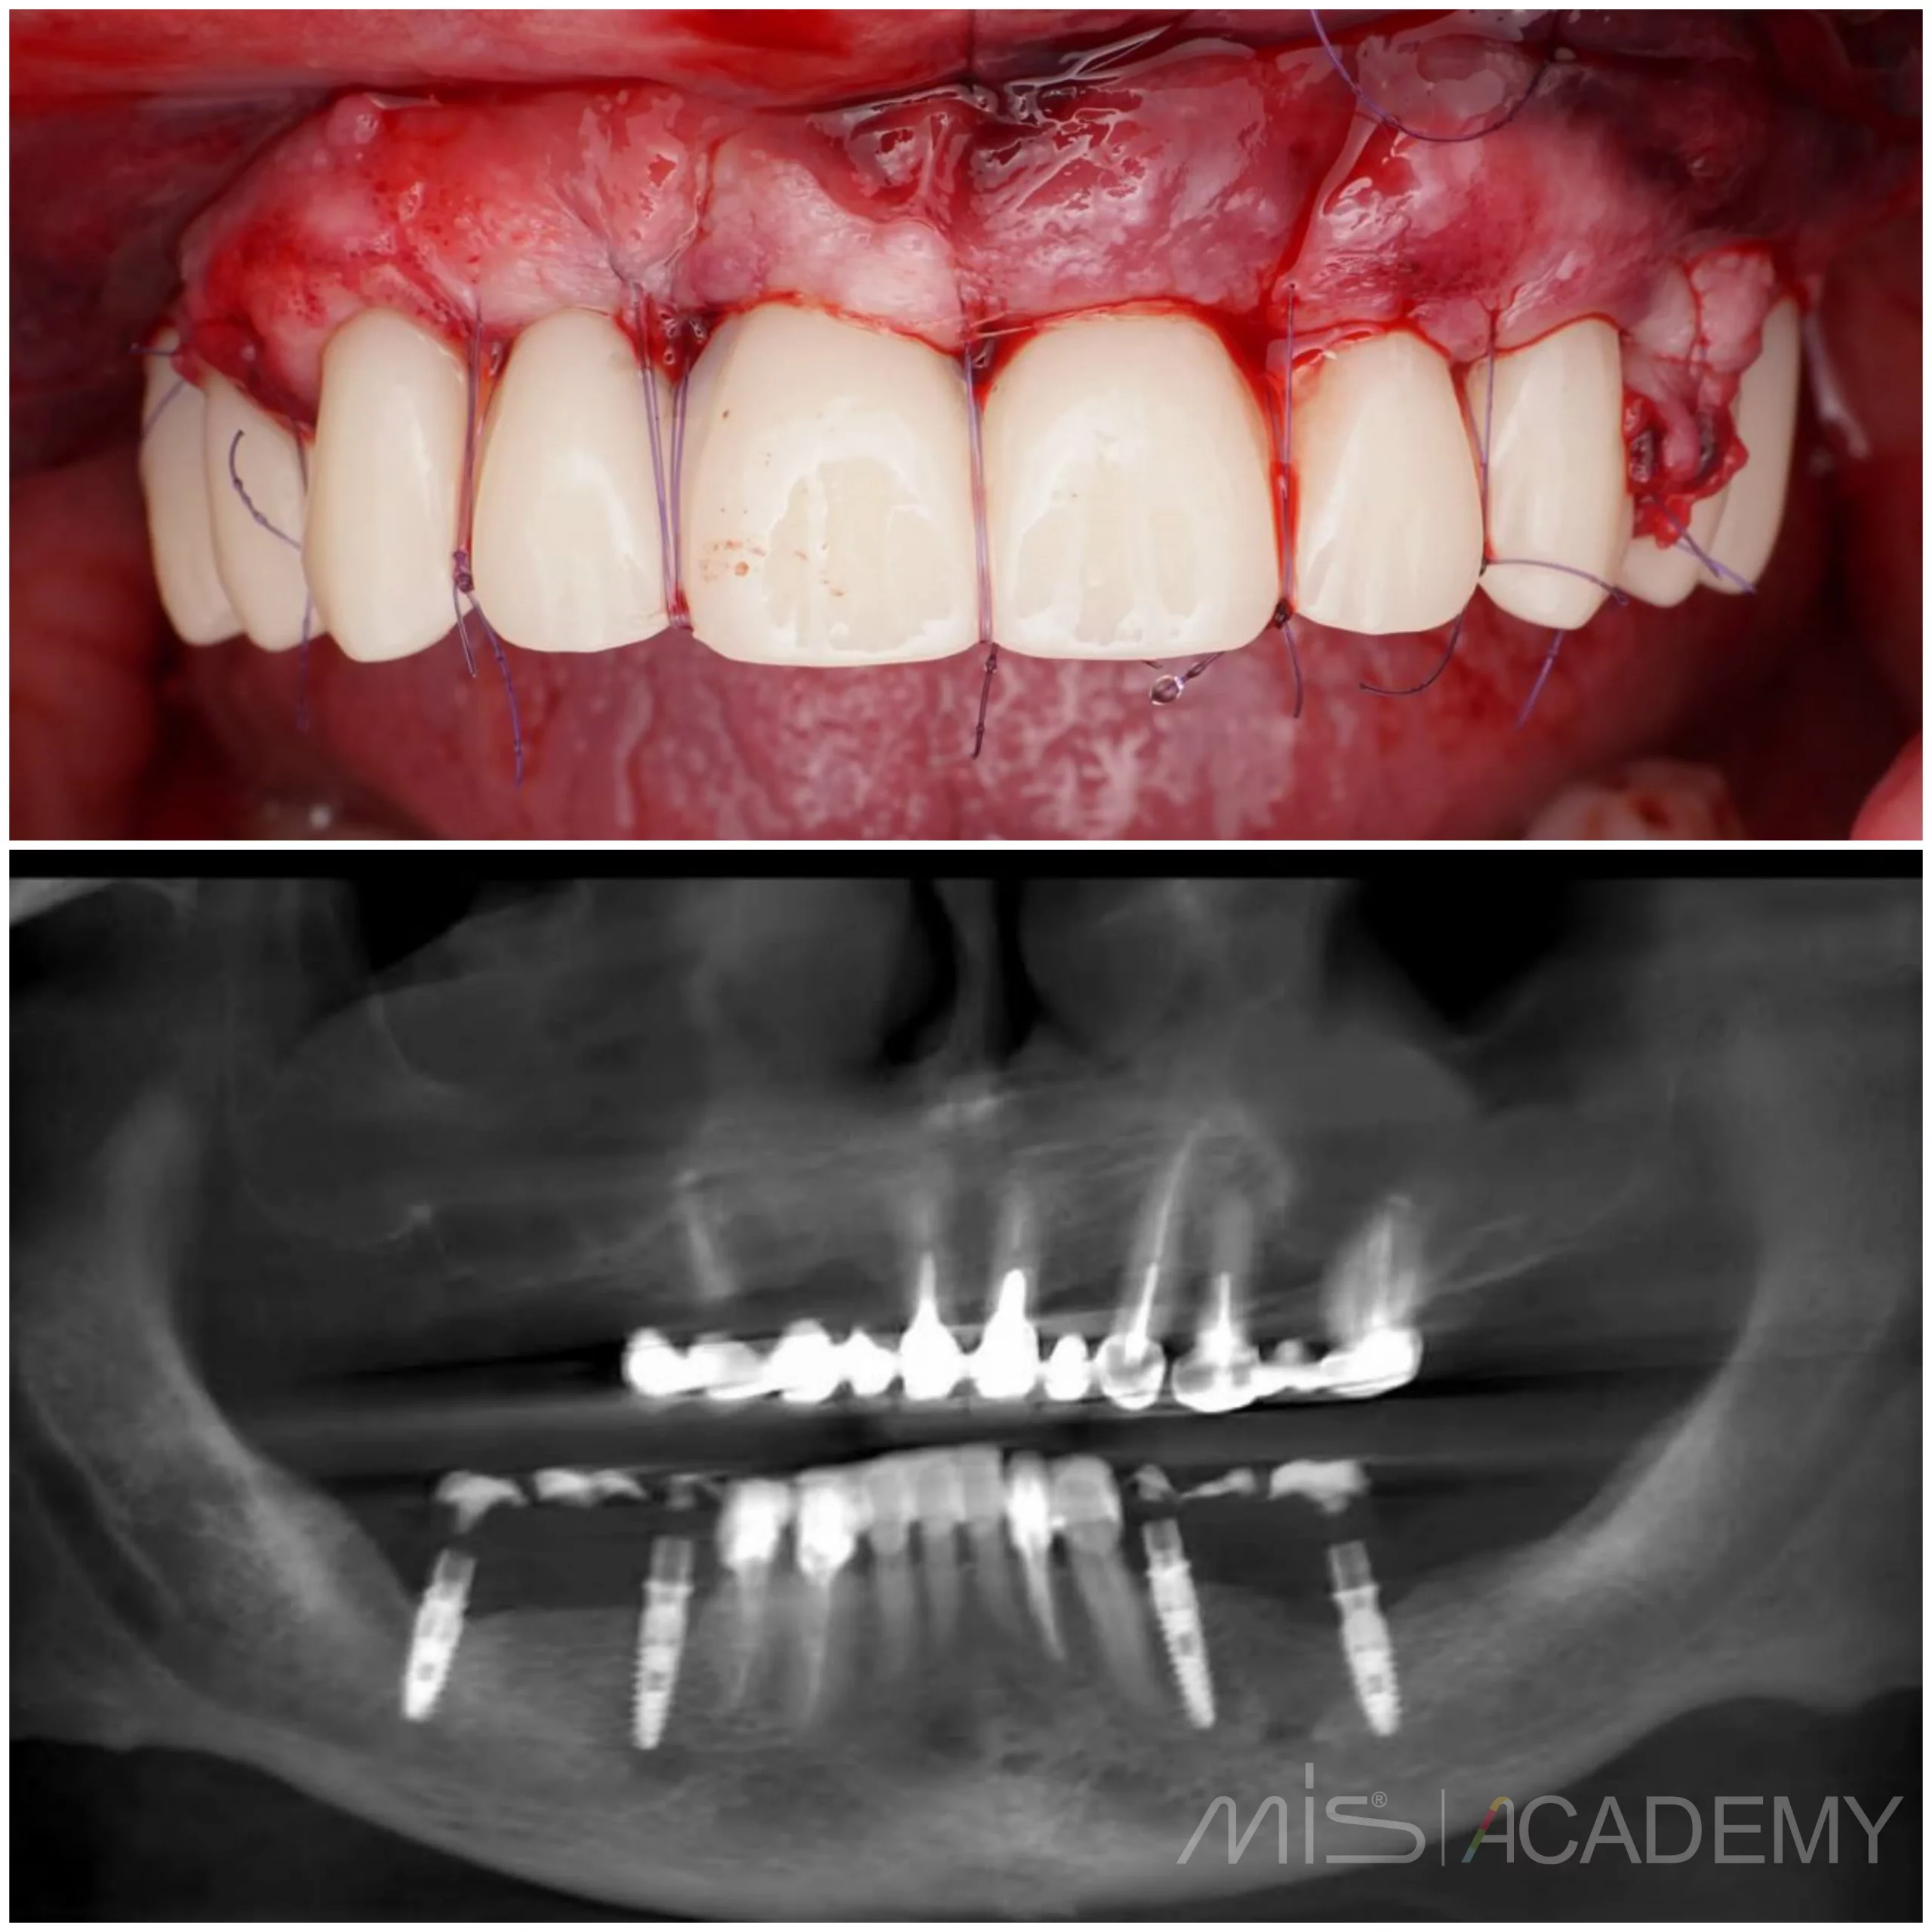

— Мягкотканная пластика.

— Балка, сварка, временный протез.

— Швы.

— Осмотр и снятие швов через 2 недели.